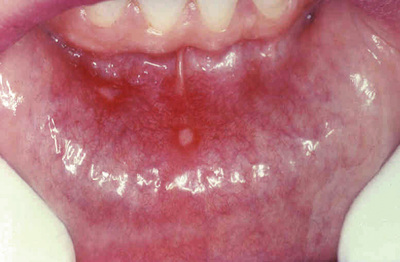

These common superficial mucosal ulcerations affect up to 40% of the population. They are more frequent in the first 2 decades of life, extremely painful, and often recur. Although the cause of aphthous ulcers is unknown, they tend to be familal and may be associated with celiac disease, inflammatory bowel disease, and Behçet disease. Ulcers can be solitary or multiple; typically, they are shallow, with a hyperemic base covered by a thin exudate and rimmed by a narrow zone of erythema (Fig. 15.1). In most cases they resolve spontaneously in 7 to 10 days but can recur.